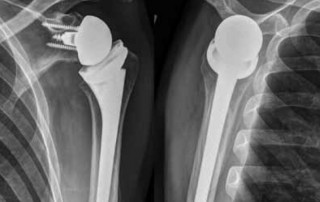

Irreparable Rupturen der Rotatorenmanschette

Ein Überblick über die aktuellen Therapieoptionen MÜNCHEN - Die operative Behandlung der nicht rekonstruierbaren Rotatorenmanschetten-Läsion stellt eine Herausforderung für den behandelnden Orthopäden dar. Allerdings stehen heute ausgezeichnete arthroskopische und [...]